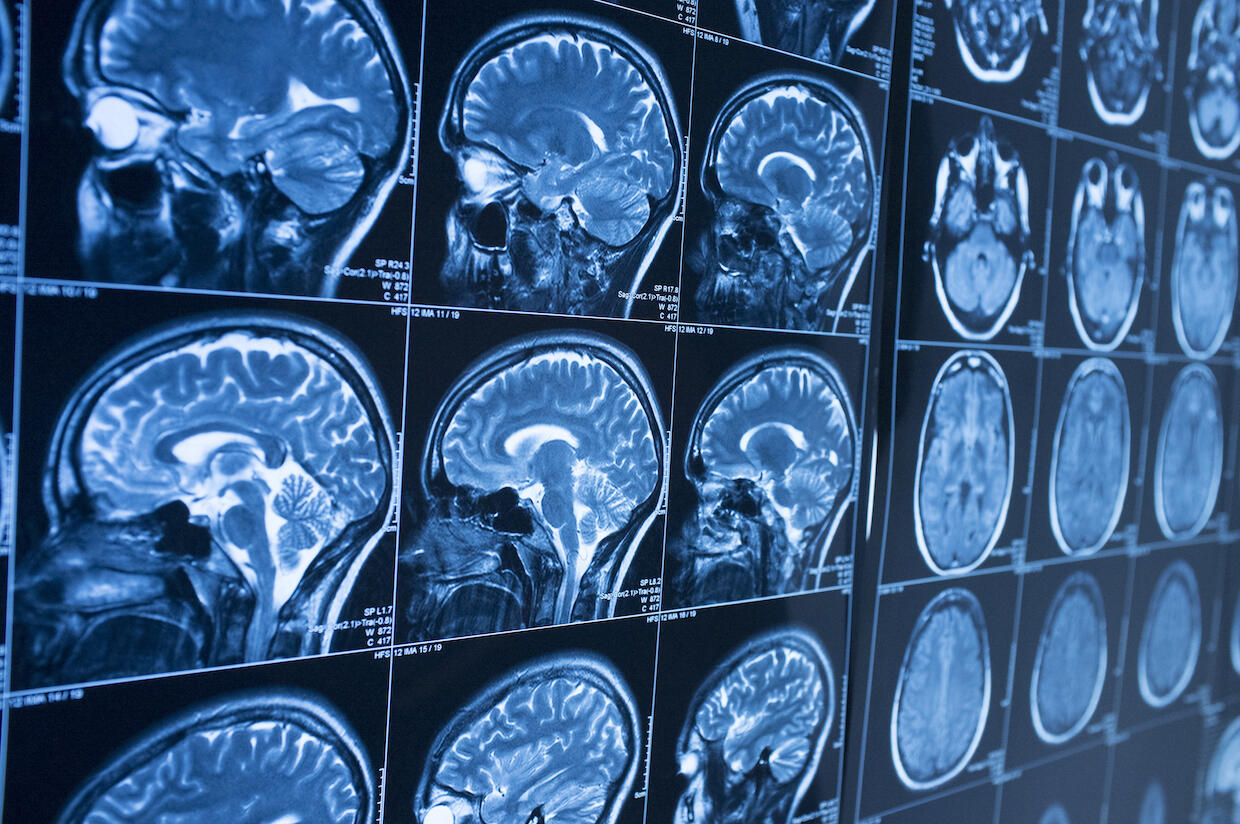

Predictive deep brain stimulation and minimally invasive procedures will be among the advances in neurosurgery in the coming years, VCU experts say. (Getty Images)